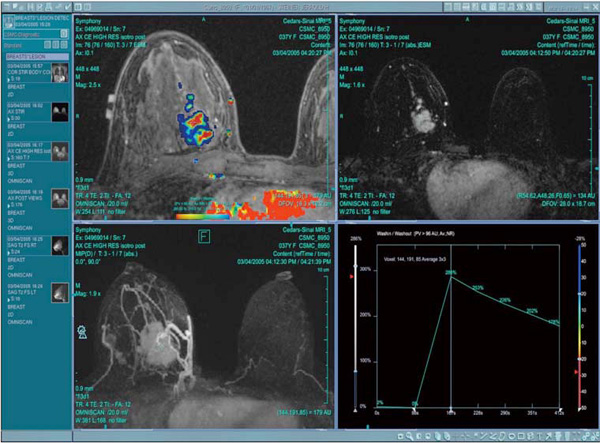

ダイナミック検査における良悪性の鑑別を視覚的にもわかりやすく,カラーにてマッピング表示します。Time-Intensityカーブと同期することにより,診断のしやすい画像を提供することが可能です。もちろんカラーマッピングは元データ,加工されたデータ双方にて作成できます。

Functional Analysis